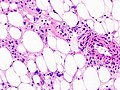

Features:

- Smooth muscle.

- Adipose tissue - not always present[11] - key feature.

- Abundant blood vessels.

Notes:

- May have melanin pigment - occasionally extensive.[12][13]